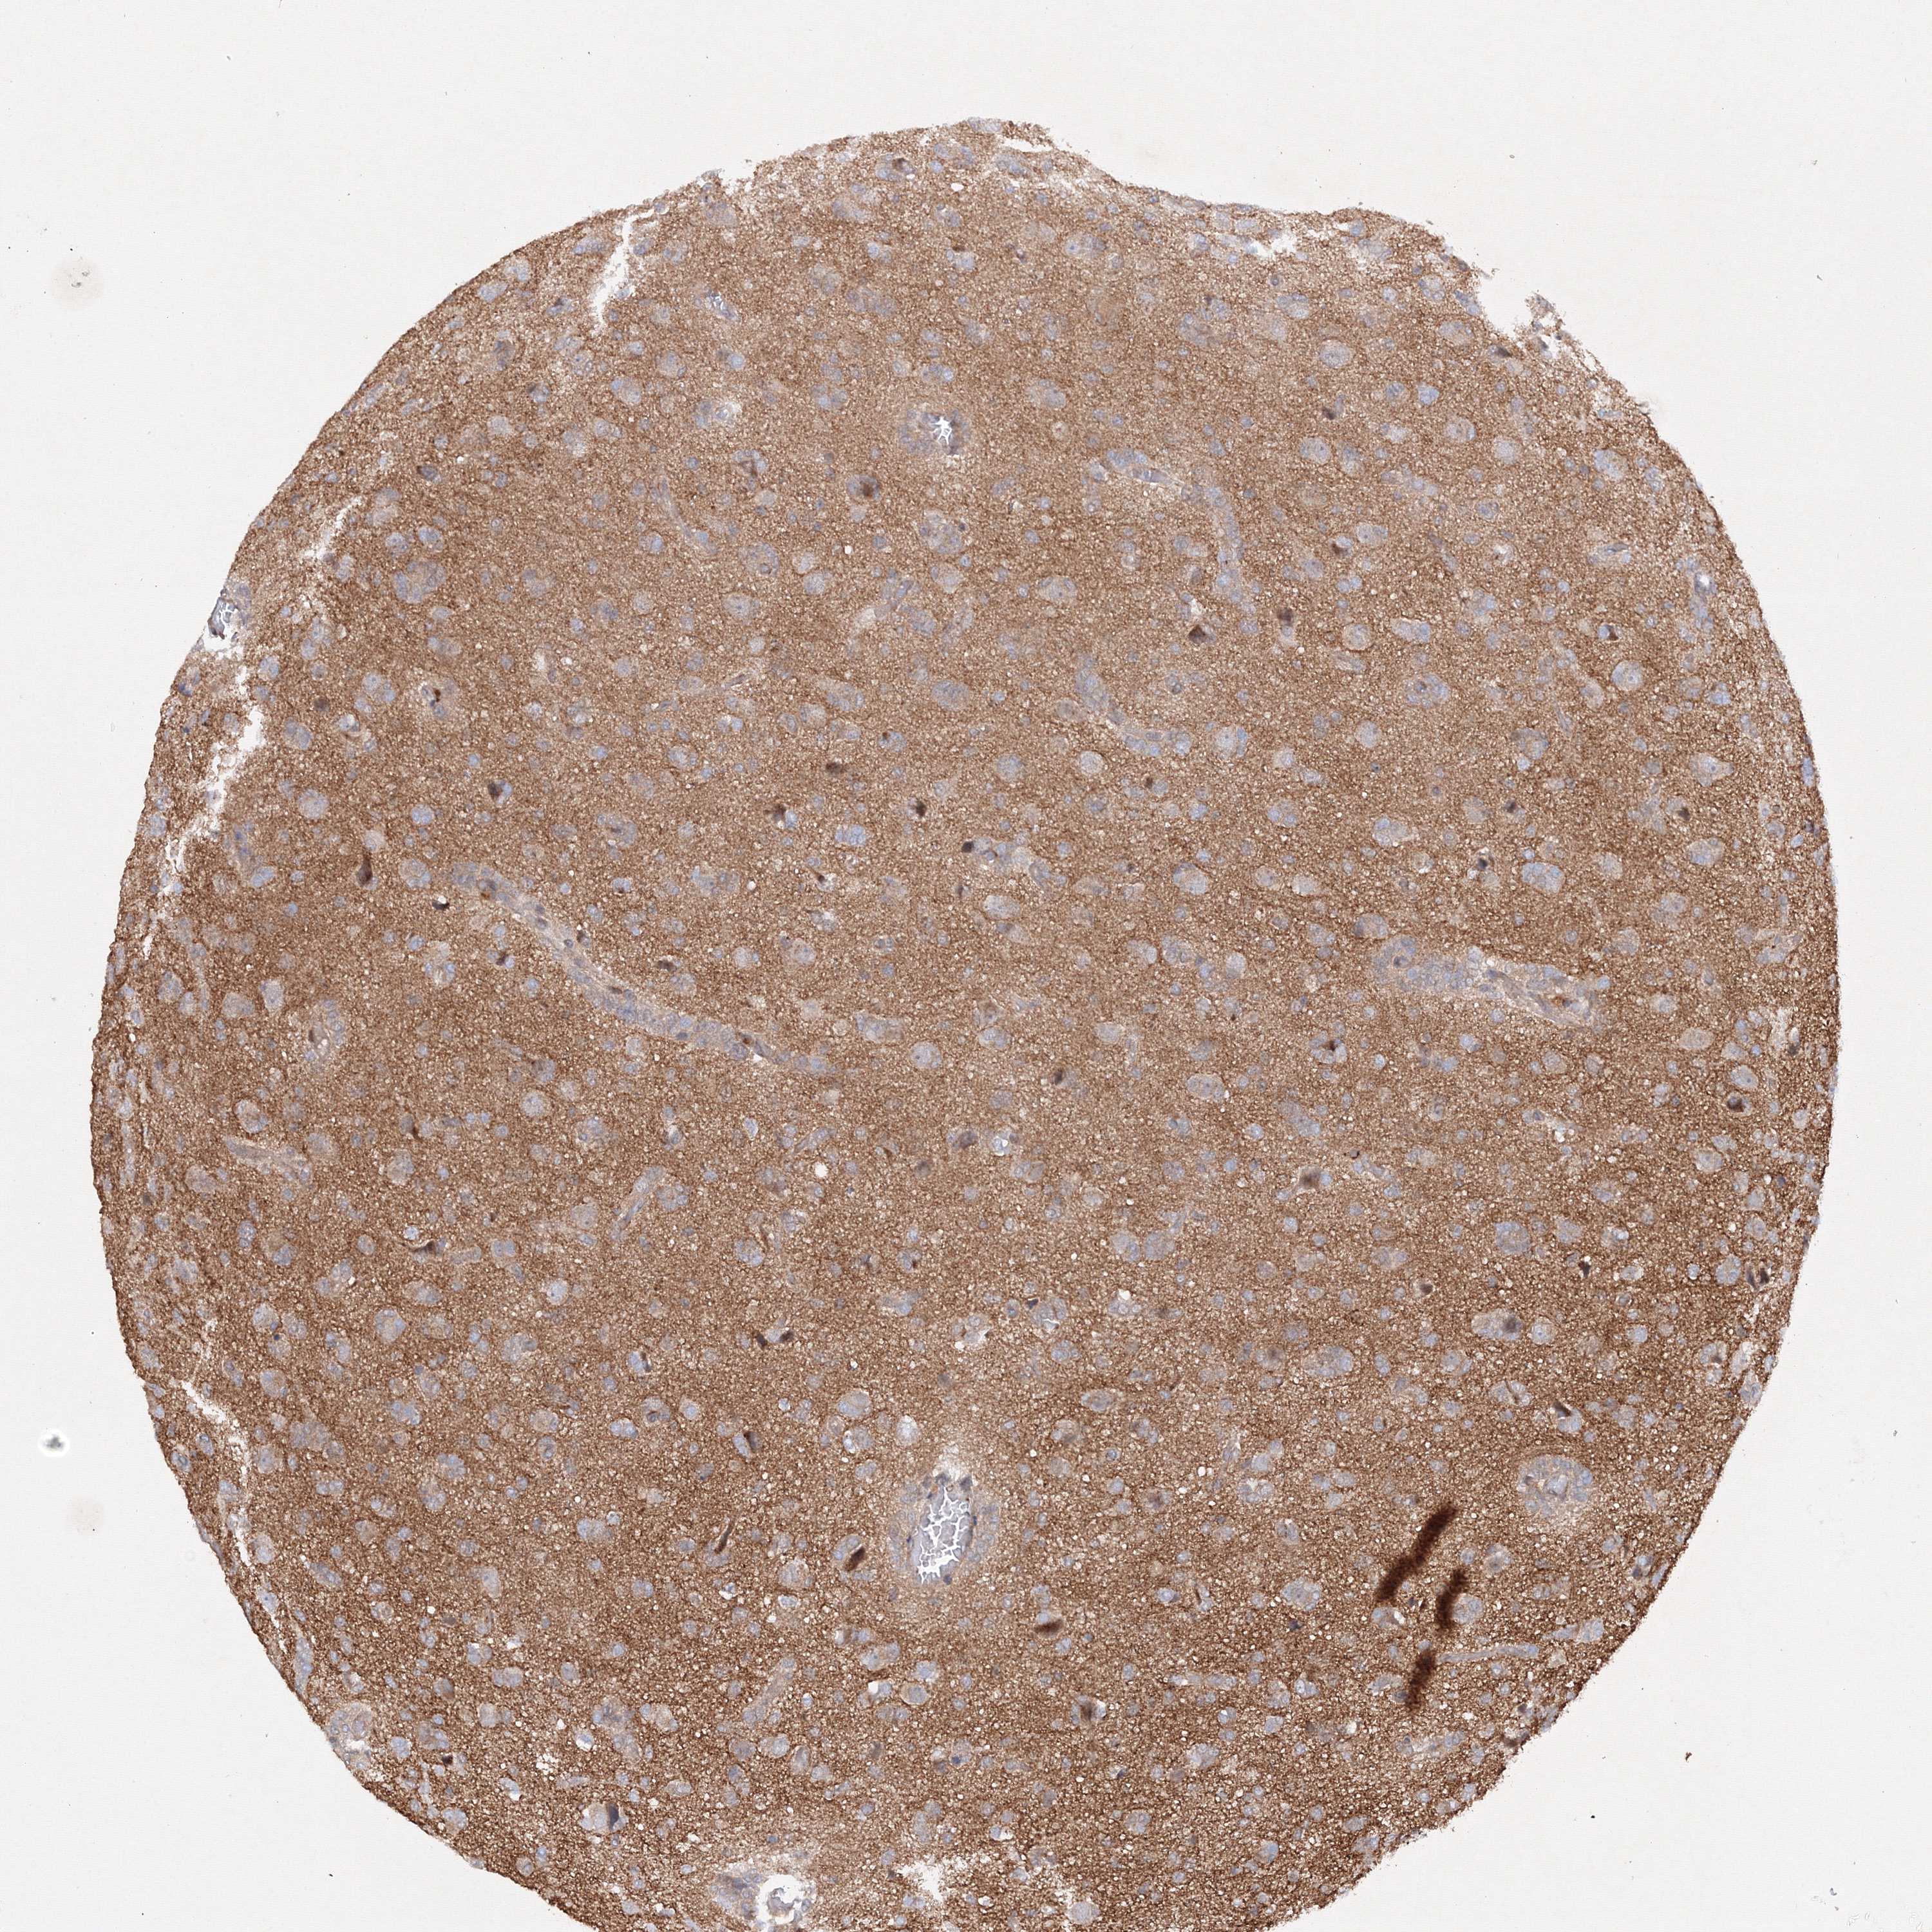

GLIOMA - Protein expressioni

A mouse-over function shows sample information and annotation data. Click on an image to view it in a full screen mode. Samples can be filtered based on level of antibody staining by selecting one or several of the following categories: high, medium, low and not detected. The assay and annotation is described here.

Note that samples used for immunohistochemistry by the Human Protein Atlas do not correspond to samples in the TCGA dataset.

Antibody stainingi

Antibody staining in the annotated cell types in the current human tissue is reported as not detected, low, medium, or high, based on conventional immunohistochemistry profiling in selected tissues. This score is based on the combination of the staining intensity and fraction of stained cells.

Each image is clickable and will lead to virtual microscopy that enables deeper exploration of all samples and also displays staining intensity scores, fraction scores and subcellular localization as well as patient and tissue information for each sample.

Antibody HPA035894

Staining

High

Medium

Low

Not detected

Intensity

Strong

Moderate

Weak

Negative

Quantity

>75%

75%-25%

<25%

None

Location

Nuclear

Cytoplasmic/membranous

Cytoplasmic/membranous,nuclear

Glioma, malignant, High grade

Glioma, malignant, Low grade

Glioblastoma, NOS